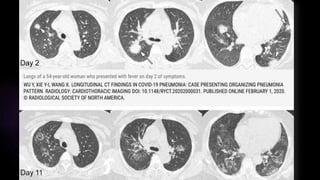

 Durante los días 0 – 2, lo predominante fue una TC normal en algo más de la mitad de los

casos y en un 44% de pacientes se encontró opacidad en vidrio esmerilado, generalmente

unilateral.

 Posteriormente, a los días 3 – 5, el hallazgo predominante fue opacidad en vidrio

esmerilado en un 88% de los pacientes seguido por consolidaciones, la afectación fue en

un 30% multilobar.

 A los días 6 -12, el hallazgo predominante fue opacidad en vidrio esmerilado con un

aumento en la frecuencia de consolidaciones, la afectación multilobar llegó al 50%.

TOMOGRAFIA EN COVID19 SEVERA – HALLAZGOS

SEGÚN TIEMPO DE EVOLUCIÓN